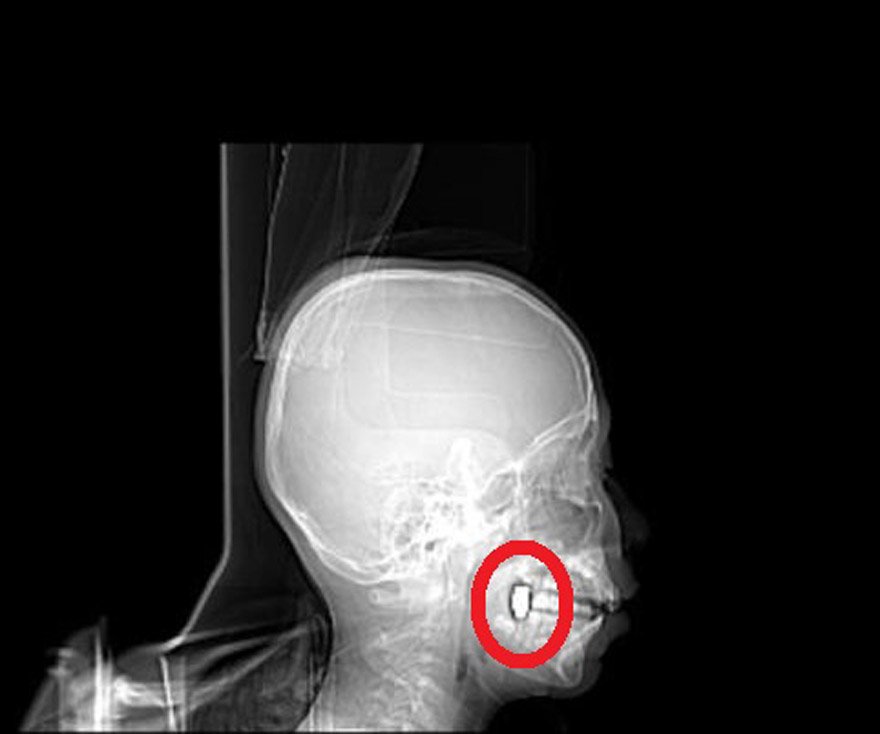

Osman Gündüz, sabaha karşı kusmaya başladı. Bunun üzerine ailesi Osman'ı Kadınhanı Devlet Hastanesi'ne götürdü. Osman Gündüz, buradan da Konya Numune Hastanesi'ne sevk edildi. Gündüz'ün burada çekilen tomografisinde başından giren mermi çekirdeğinin çenesine saplandığı belirlendi. Gündüz buradan da Selçuk Üniversitesi Tıp Fakültesi'ne gönderildi. 4 gün yoğun bakımda kaldıktan sonra normal odaya alınan Osman Gündüz'ün çenesindeki mermi çekirdeği sağlığı acısından şu an için çıkartılmadı. Gündüz'ün bir süre çenesindeki mermi ile yaşamını sürdüreceği belirtildi.

MERMİ ÇEKİRDEĞİ ÇIKARTILAMADI

Bayram Gündüz, hastanede yapılan tetkiklerde oğlunun başına mermi isabet ettiğini öğrenince şaşırdıklarını belirtti. Mermi girdikten sonra başında herhangi bir kanama olmadığını ifade eden Gündüz, çenesine saplanan mermi çekirdeğinin, şu an için çıkartılmadığını ve oğlunun bir süre mermi çekirdeğiyle yaşayacağını söyledi. Oğlunun sağlık durumunun iyi olduğunu ifade eden Gündüz, ''4 gün yoğun bakımda kaldıktan sonra şu an normal odaya alındı. Tedavisi sürüyor. Sağlığı iyi durumda; ancak yürümekte güçlük çekiyor'' diye konuştu.